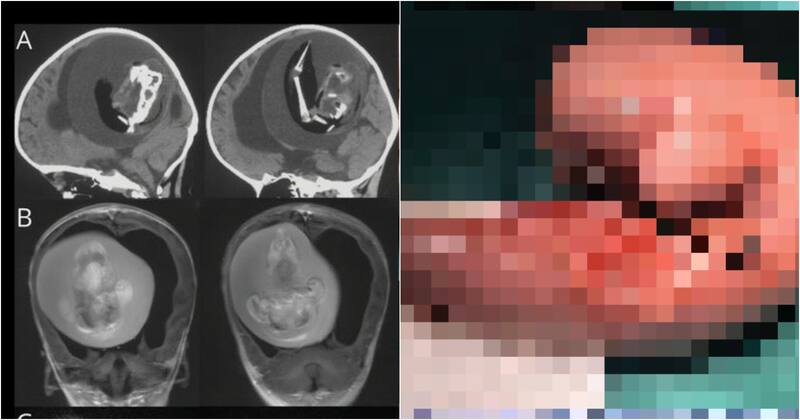

Un caso realmente excepcional fue el que vivió una familia china, donde una menor de solo un año tuvo que someterse a una intervención cerebral para extraerle el feto de su hermano gemelo.

Lo impactante de este caso es que generalmente cuando sucede esta situación, el feto llamado “gemelo parásito” se aloja en el abdomen de su hermano, y no en el cerebro.

La pequeña mostraba un retraso en el desarrollo de las habilidades motoras y la circunferencia craneal un poco más grande de lo normal. Cuando le retiraron el feto, este tenía sus brazos e incluso algunos dedos.

“Los estudios revelaron que el feto contenía una columna vertebral y dos huesos de la pierna, concretamente el fémur y la tibia, junto a “brotes” en forma de extremidades superiores y dedos”, declaró.